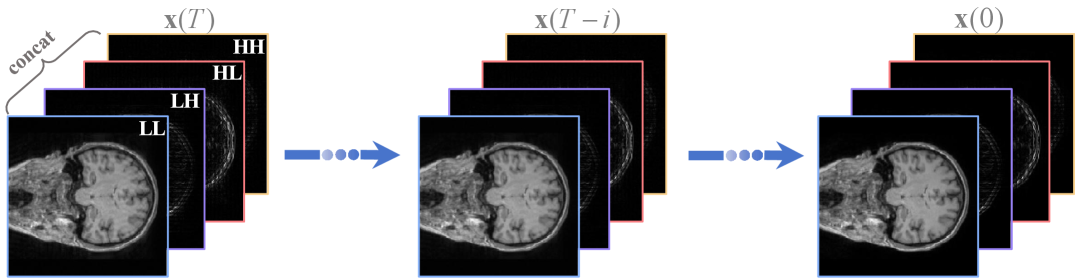

We decompose the input image into four wavelet subbands: LL, HL, LH, and HH via the DWT. As shown in Fig. 2, the wavelet domain components are fed into the network, the score function is obtained in the wavelet domain, and then converted to the image domain for continuous iteration. The above process is equivalent to performing a diffusion process in the wavelet domain, as shown in Fig 3. Benefiting from the reduction of input image resolution, the testing time of the proposed model is reduced.